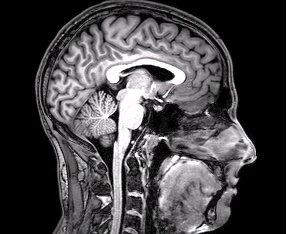

虽然准确解释为什么我们似乎感知整个视野需要神经科学研究,但这里有一个可能的理论解释,基于Dennett的多重草稿模型。我们的眼睛接收大量视觉信息,早期视觉皮层对其进行处理。然后更高级的视觉信息在大脑中变得可用。因为所有数据都在那里,所以每当我们的注意力集中在视野的任何给定部分时,我们发现我们可以看到它。所有其他周边项目仍然可用,我们也可以快速将注意力转移到它们上。因此,我们的视野就是许多视觉神经元同时激活传递信息。不需要在某个笛卡尔剧场中重新广播所有数据。每当我们深入注意到某些东西时,我们的大脑只是突出已有数据的特定部分。